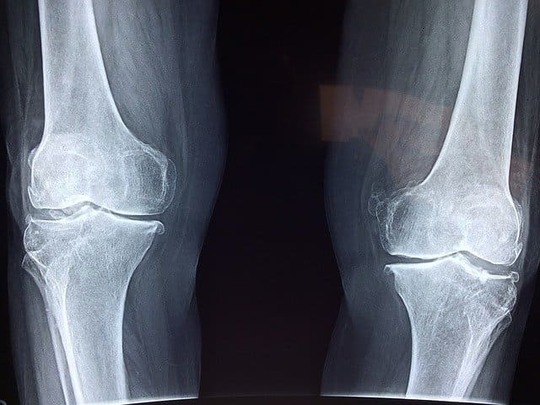

突き指の程度が重い場合は、伸筋腱の損傷も大きいです。多くの場合、伸筋腱が切れたり末節骨に剥離骨折が起きたりしています。第一関節が常に曲がった状態になり、放っておくと第二関節が過剰に伸び指が変形する可能性があります。

第一関節に亜脱臼が起きたり、中節骨にまで力が加わり骨折や脱臼が起きたりすることもあります。このような場合は、指を動かすことが難しくなり、激しい痛みや腫れが起こります。

骨折している場合は段々と痛みが強くなる

突き指は時間が経つとともに段々と痛みが引いていきます。しかし、骨折している場合は、段々と痛みが強くなります。

怪我をした直後の5~15分以内に、指の形が変わるくらいまでの強い腫れが起こった場合は骨折をしている可能性が高いです。